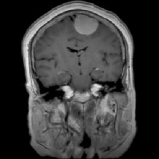

4.1.6 Brain MRI

Brain tumors pose significant health challenges, often impacting critical functions such as vision, balance, and cognition. Early detection is crucial for improving patient outcomes and quality of life. Through MRI scans, different conditions of the brain can be visually detected. The selected brain tumor dataset 666https://www.kaggle.com/datasets/sami009mr/brain-tumor-dataset contains 3,362 images across four categories: glioma, meningioma, pituitary tumors, and normal brains. Images illustrating the three aforementioned classes can be found in Fig. 7.